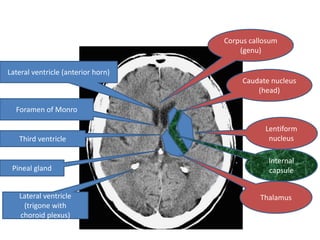

Corpus callosum (genu) Lateral ventricle (anterior horn) Caudate nucleus (head) Foramen of Monro Lentiform Third ventricle nucleus Internal Pineal gland capsule Lateral ventricle Thalamus (trigone with choroid plexus)